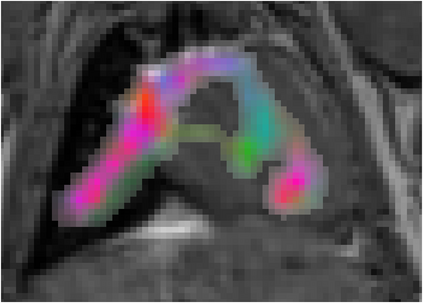

Various imaging modalities allow for time-dependent image reconstructions from measurements where its acquisition also has a time-dependent nature. Magnetic particle imaging (MPI) falls into this class of imaging modalities and it thus also provides a dynamic inverse problem. Without proper consideration of the dynamic behavior, motion artifacts in the reconstruction become an issue. More sophisticated methods need to be developed and applied to the reconstruction of the time-dependent sequences of images. In this context, we investigate the incorporation of motion priors in terms of certain flow-parameter-dependent PDEs in the reconstruction process of time-dependent 3D images in magnetic particle imaging. The present work comprises the method development for a general 3D+time setting for time-dependent linear forward operators, analytical investigation of necessary properties in the MPI forward operator, modeling aspects in dynamic MPI, and extensive numerical experiments on 3D+time imaging including simulated data as well as measurements from a rotation phantom and in-vivo data from a mouse.